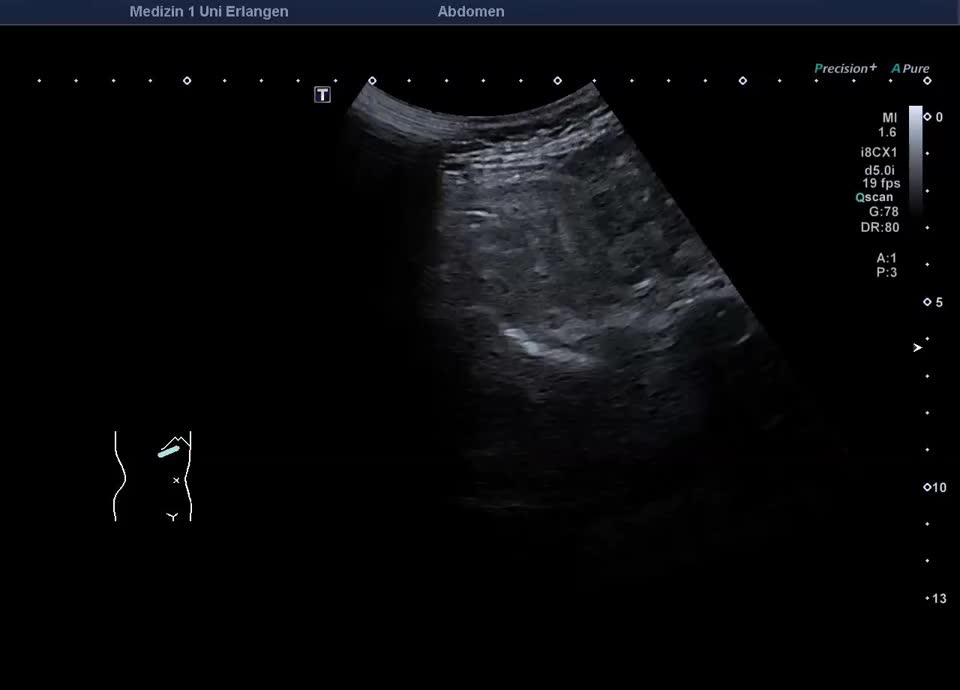

Lobuläre Mehrverfettung des rechten Leberlappens (siehe auch nächstes Bild)

Focal fatty infiltration

Fokale Mehrverfettung